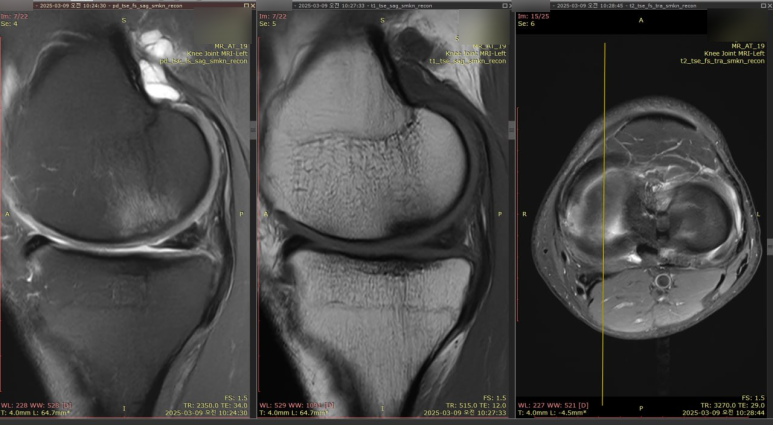

하지만 가져오신 MRI 영상과

환자분의 무릎을꼼꼼히 살펴본 결과

진짜 범인은 따로 있었습니다.

MRI 상 반월판 손상은 보였지만

선명하고 밝은 급성 파열선이 아닌

오랜 시간 달리며 닳아진

'퇴행성 변화' 였던거죠.